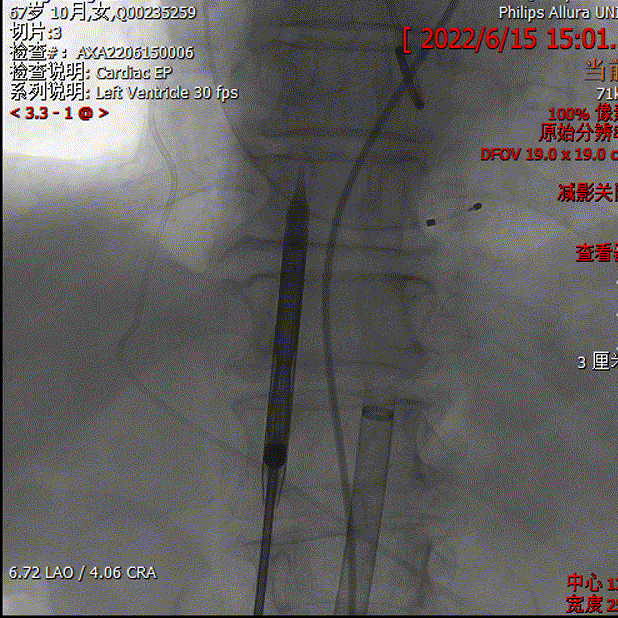

主动脉根部造影

检查挂角

导丝跨瓣

测术前压差